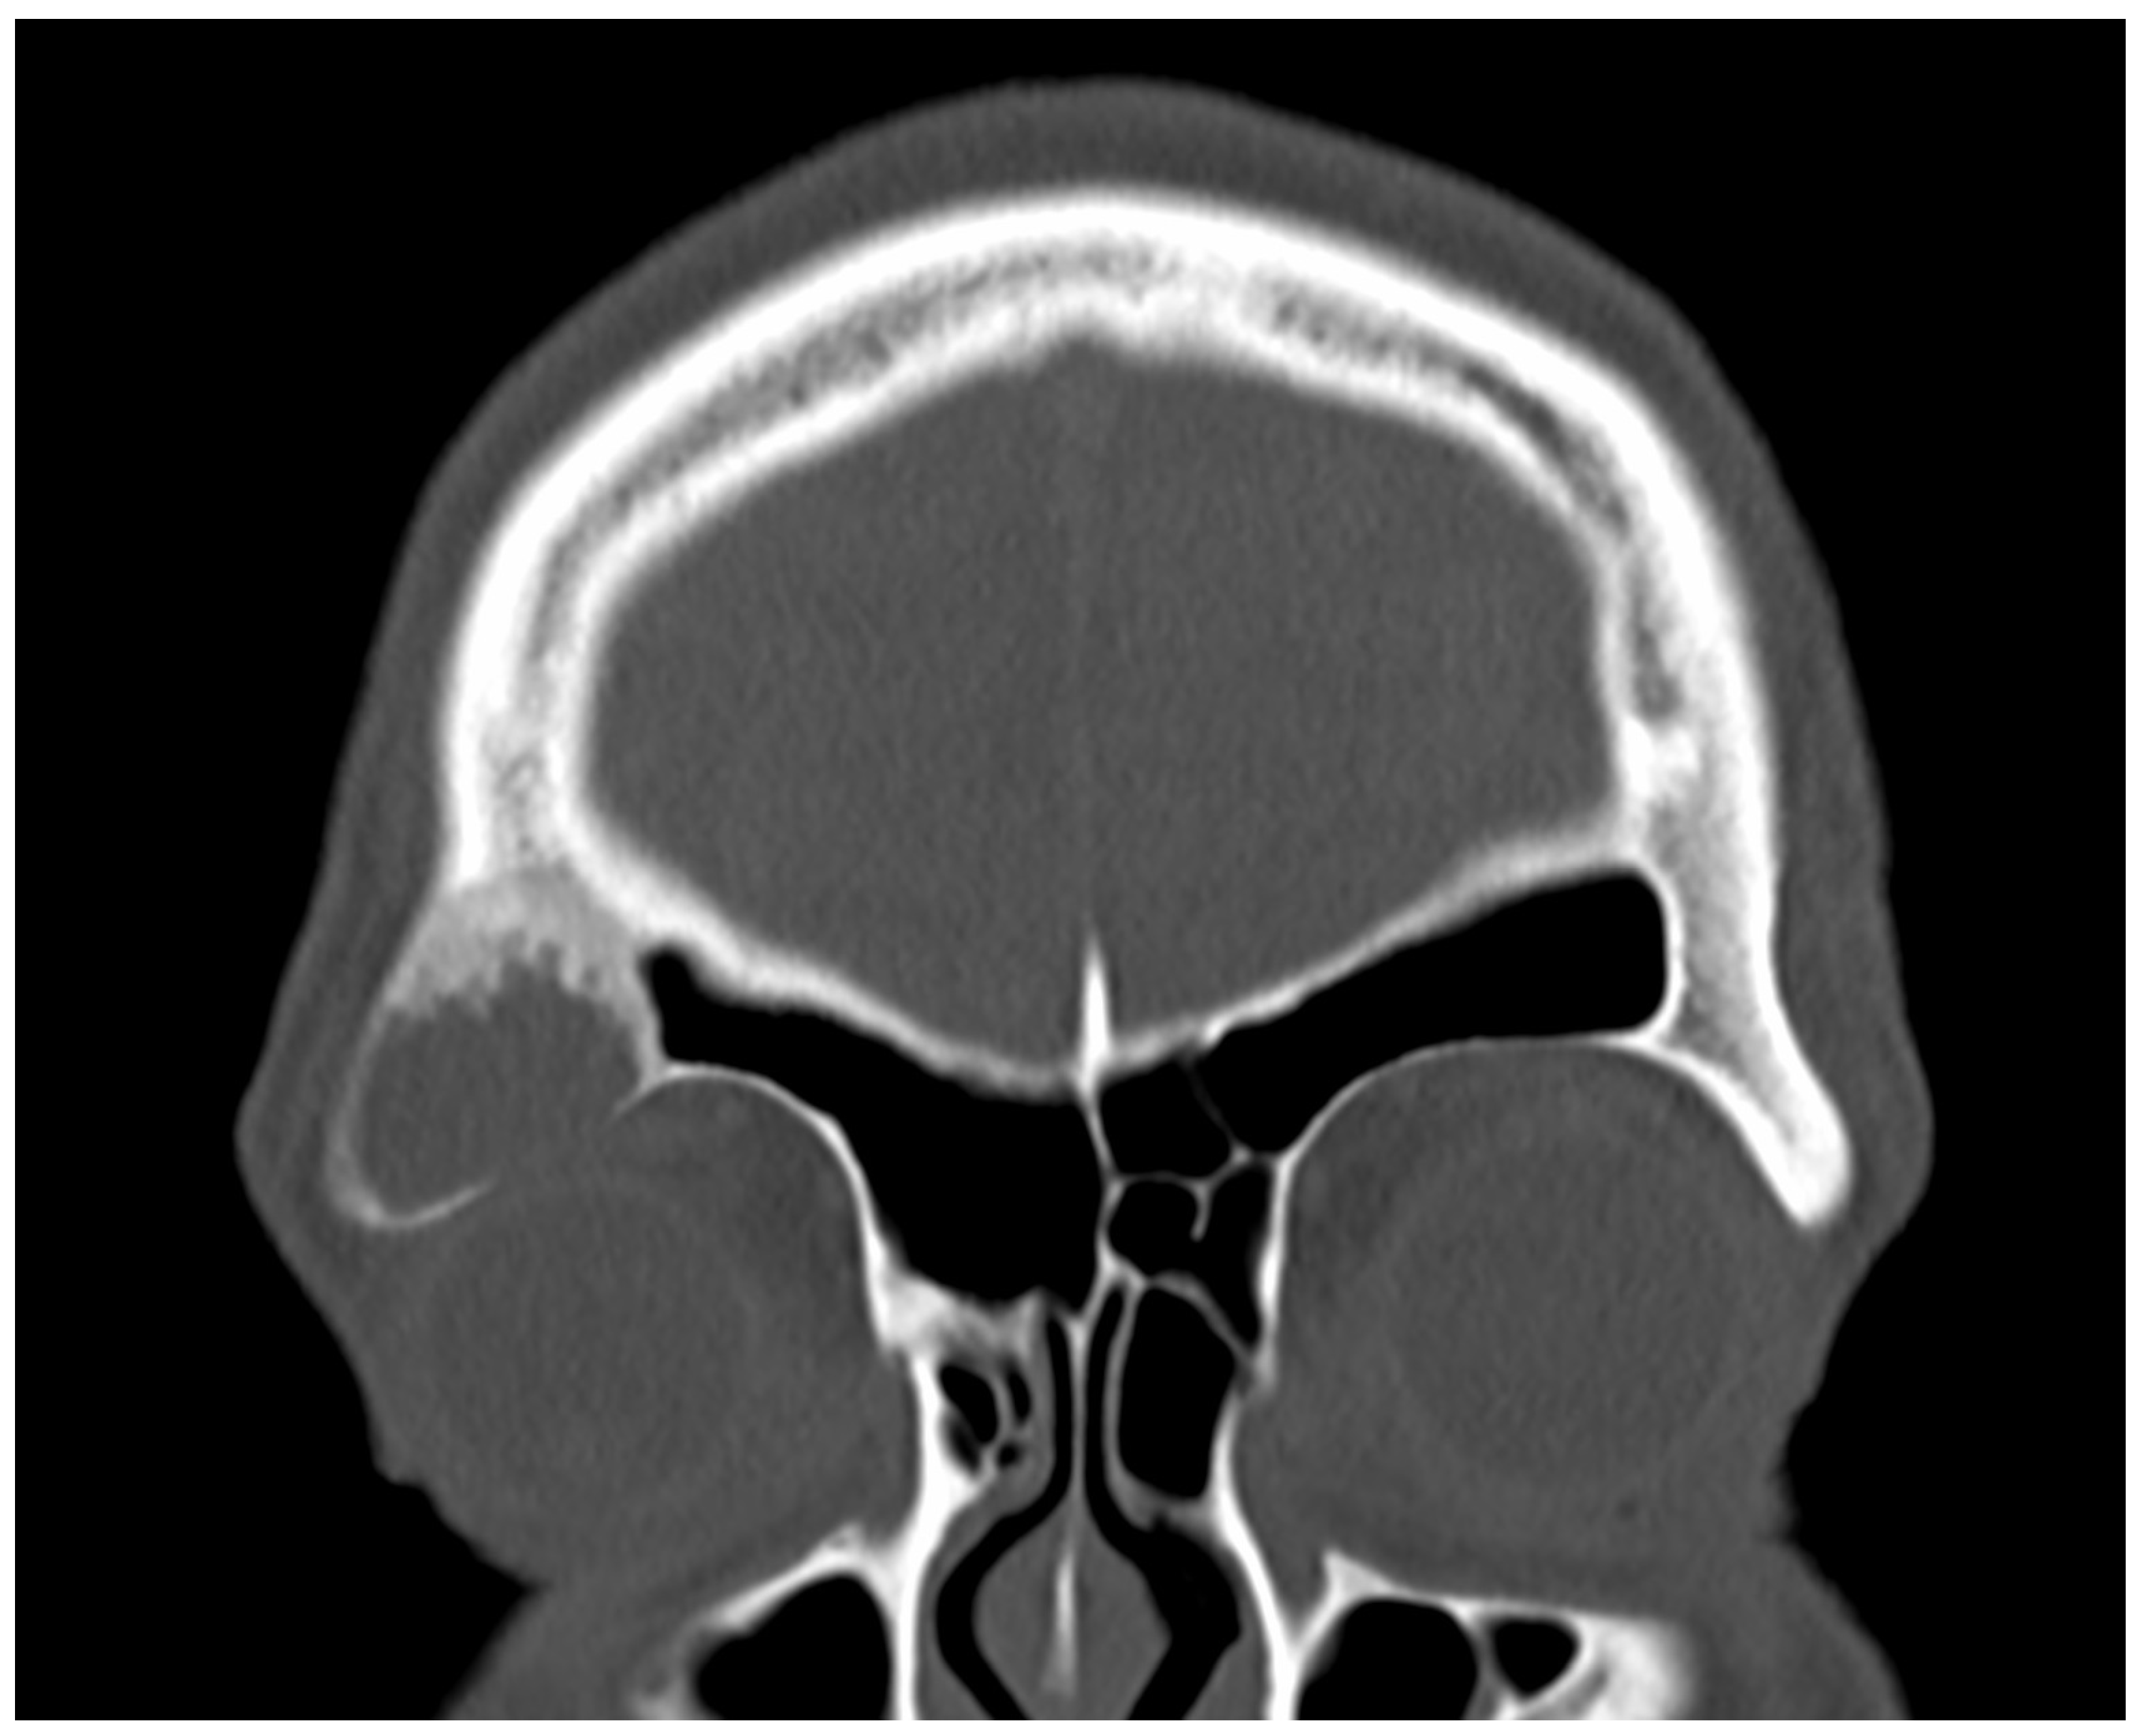

Figure 1. A 38-year-old male presented to the emergency outpatient clinic with sudden-onset headache, nausea, and general discomfort. Neurological and otorhinolaryngological examinations and laboratory analyses revealed no abnormalities. Cranial CT did not indicate any neurovascular events but incidentally detected a cystic, osteodestructive lesion measuring 2.5 cm in diameter in the right frontal sinus. Based on its location, characteristics, and the patient’s history of recurrent frontal headaches and retrobulbar pressure, a mucocele was initially suspected. As the patient’s acute complaints resolved on symptomatic therapy quickly, we decided on elective surgery to drain the plausible mucocele. Due to the lesion’s far lateral position, an endonasal approach was impractical, leading to a supraorbital external approach. A right-sided frontal bone window was created using a piezo device. During the removal of the frontal bone cap, yellowish turbid fluid was discharged from the frontal sinus. The fluid was totally aspirated, and the suspicious mucosa was completely excised and sent for histological analysis. The bony floor of the frontal sinus was found to be thinned and partially eroded, exposing the underlying periorbita, which appeared intact and healthy. The clinical appearance during surgery reinforced the mucocele diagnosis. Subsequently, the bone cap was repositioned, and the external wound was securely closed. The surgery proceeded without any intra- or postoperative complications. Fibrous histiocytoma, or dermatofibroma, is one of the most common cutaneous soft tissue lesions [1]. However, it hardly ever occurs in the skeleton. Its incidence among surgically treated benign skeletal lesions is approximately 1% [2]. The occurrence of benign fibrous histiocytoma in the skull is rarely described in the literature. To our knowledge, this present case is the first confirmed benign fibrous histiocytoma in the frontal sinus. Only one was reported earlier in this location; however, this was a malignant tumor [3]. The first ever reported benign fibrous histiocytoma in the paranasal sinuses was described by Townsend et al. in 1973 [4]. Considering the extremely rare localization and the potential for malignization, the case was presented to the interdisciplinary TUMOR-Board. Since R0 resection is neither clinically nor histologically confirmed and the risk involved in revision surgery is high, close monitoring was chosen, in view of the approximately 11% recurrence rate reported by Bielamowitz et al. [5]. The patient has remained symptom-free without evidence of recurrence, as confirmed by clinical and imaging assessments.